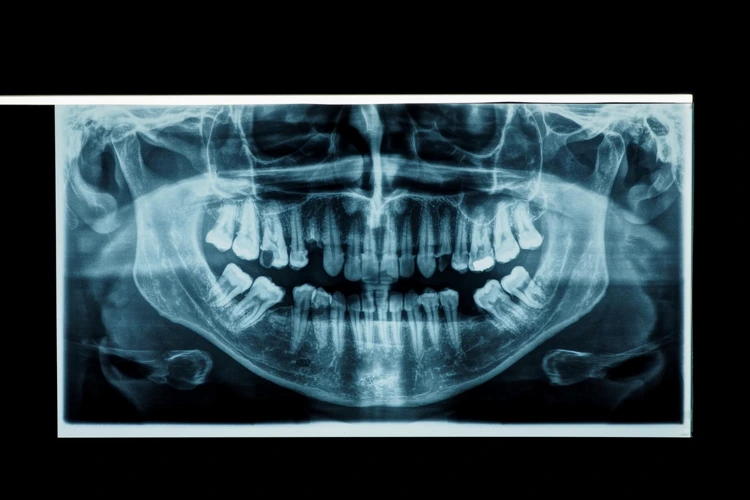

Dental X-rays, also referred to as dental radiographs, produce detailed images of the teeth, gums, and surrounding structures, providing important information about oral conditions that may not be visible during a standard visual examination.

These images can reveal cavities between teeth, track the development of emerging teeth, assess bone levels, and identify tumours or other irregularities. Dental X-rays are also used to evaluate the position of wisdom teeth, particularly where their alignment may lead to discomfort or complications.

Dental X-rays are a non-invasive diagnostic procedure commonly used in dental care to support early identification of potential issues and inform appropriate treatment planning.